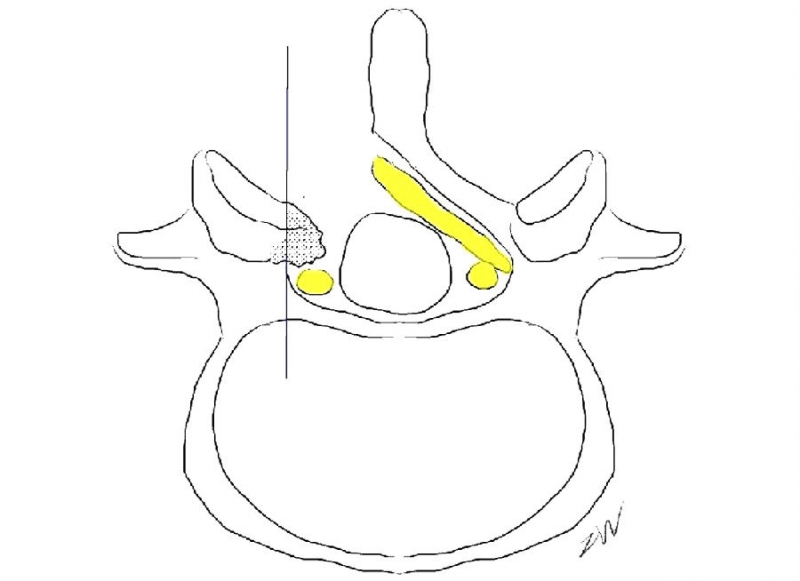

UBE处理椎管狭窄病例时,对于侧隐窝狭窄的患者,同侧减压范围与椎弓根内缘平齐即可。

从标本上看,椎弓根其实就位于终板的下方,这是术中判断椎弓根位置的解剖标志。

与椎间盘的下缘平齐即是椎弓根的上缘。

去除部分椎板上缘骨质尤其是与上关节突结合的部位利于黄韧带的切除及椎弓根内壁的显露。这个部位显露神经根的风险最小。